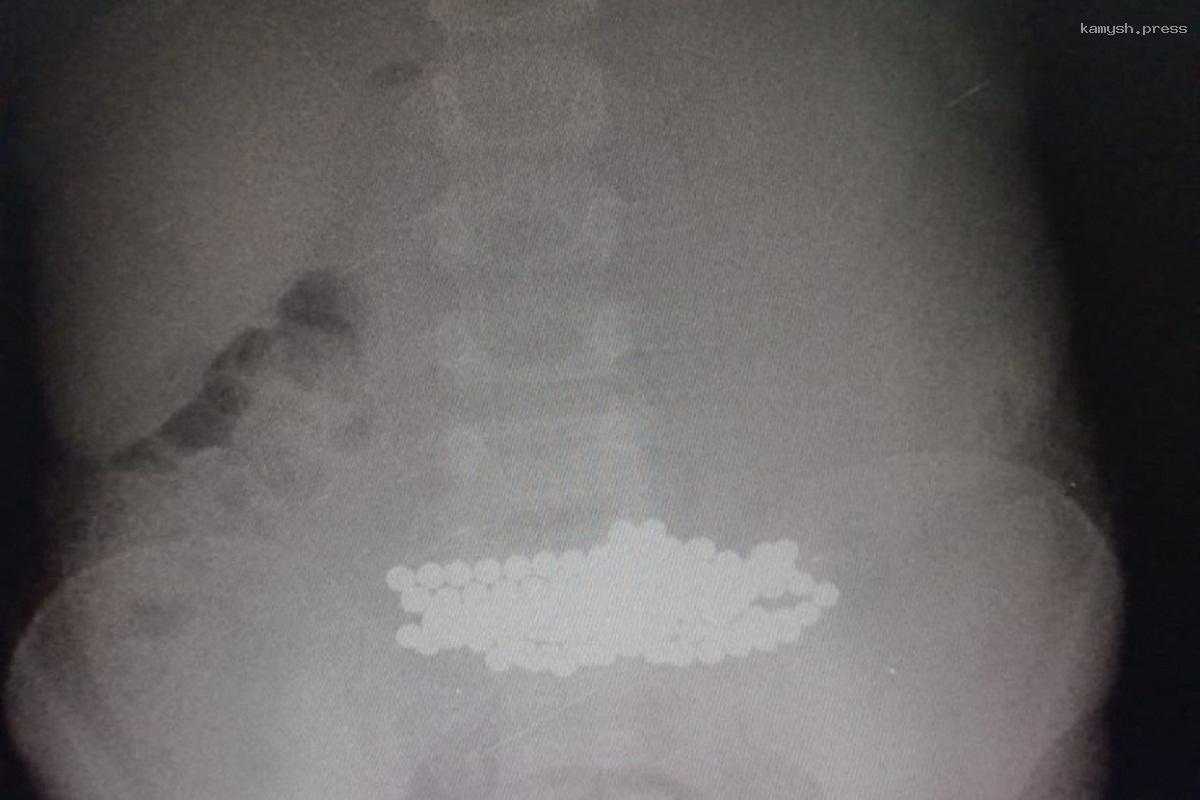

Двухлетний ребенок из природного любопытства проглотил более 100 цветных магнитных шариков. Врачи извлекли их с помощью эндоскопа.

Врачи Детской областной больницы в Ленобласти спасли двухлетнего ребенка, проглотившего более 100 цветных магнитных шариков.

В результате врачи извлекли более 100 магнитов с помощью эндоскопа. Остальные пришлось удалять хирургическим путем.